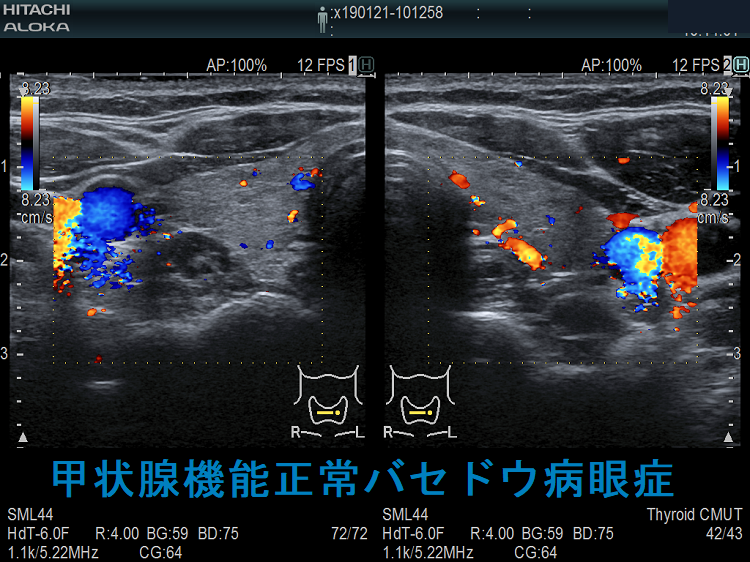

長崎甲状腺クリニック(大阪)では、メルカゾール(5mg)0.5T/日投与により数年間、甲状腺機能正常を維持している安定したバセドウ病患者にいきなり遅延型バセドウ病眼症が起こりました。そのMRI画像がこれです。

同じく、甲状腺亜全摘出20年後発症した遅延型バセドウ病眼症もありました。